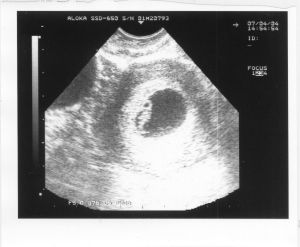

卵子受精後即開始有絲分裂,並在一邊分裂的同時一邊向子宮腔方向移動。受精卵在輸卵管內36小時後分裂為2個細胞,72小時後分裂成16個細胞,叫桑椹胚。受精後第4日,細胞團進入子宮腔,並在子宮腔內繼續發育,這時,細胞已分裂成48個細胞,成為胚泡準備植入。胚泡可以分泌一種激素,幫助胚泡自己埋入子宮內膜。受精後第6-7日,胚泡開始著床。著床位置多在子宮上1/3處,植入完成意味胚胎已安置,並開始形成胎盤,孕育胎兒了。

2、植入囊胚(又稱胚泡)附著在子宮內膜後,內膜上皮細胞的胞膜逐漸消失,變為多核細胞體。滋養層也分化為兩層,內層保留細胞膜,稱細胞滋養層;外層細胞膜消失,稱合體滋養層。合體滋養層有很強的侵蝕力,侵蝕子宮脫膜,形成小缺口,使胚泡慢慢地陷入到子宮內膜緻密層下。到受精後約第10天,整個胚泡位於子宮內膜中,第11天在子宮內膜處有小血塊和細胞碎片構成的閉鎖栓,第12天胚泡幾乎全部被增生的上皮所覆蓋,並形成一個小隆起,著床即完成。

桑椹胚從宮腔中吸收營養,宮腔液滲入到桑椹胚內,細胞分裂增生,至受精後約96小時,發展成為囊胚。囊胚的構成:①由外周的細胞群構成滋養層;②被滋養層包圍的間隙,含有液體,稱為囊胚腔;③位於囊胚腔一端的細胞群,稱為內細胞群,以後發展成為胚胎。桑椹胚進入子宮腔後呈游離狀態約3-4d。